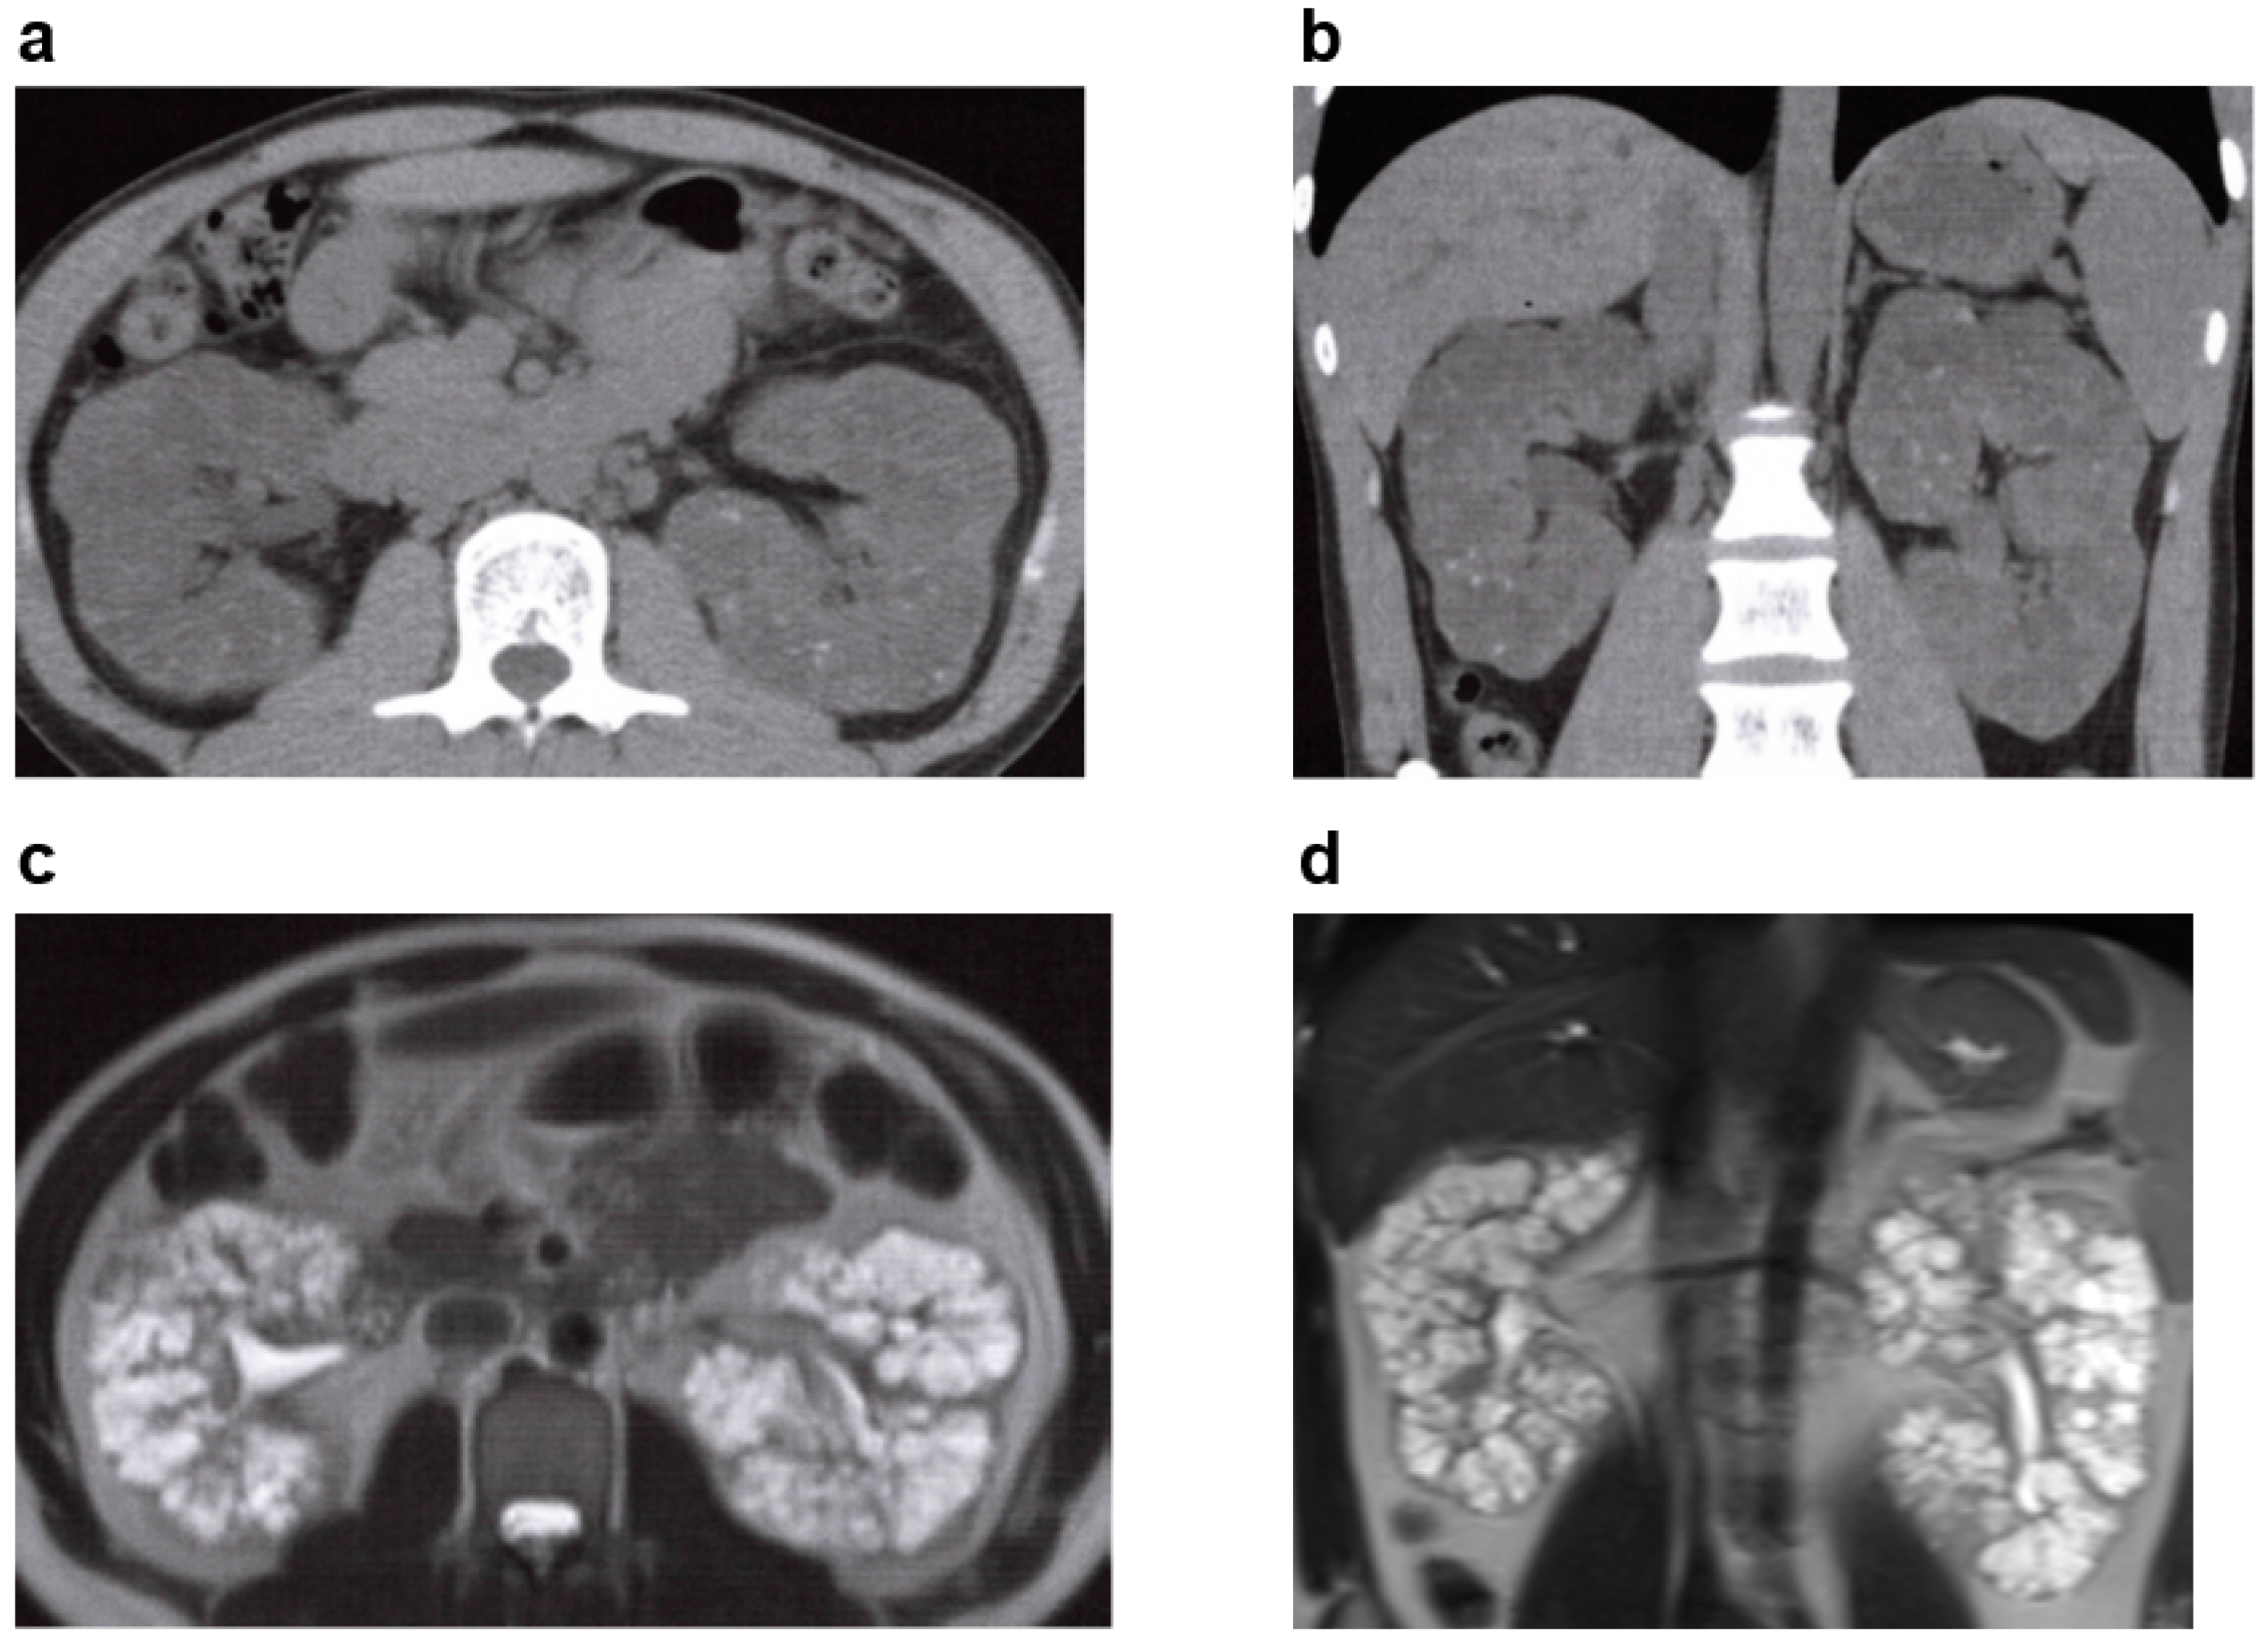

3.1. Autosomal Recessive Polycystic Kidney Disease (ARPKD)